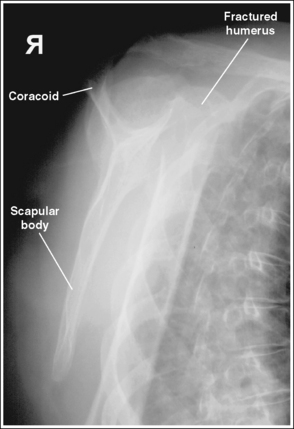

See Figures 4-86 and 4-87 and Box 4-22.

Scatter radiation is controlled. Image density is uniform across the humerus.

The humerus is in an AP projection. The medial and lateral humeral epicondyles are demonstrated in profile, and the radial head and tuberosity are superimposed over the lateral aspect of the proximal ulna by approximately 0.25 inch (0.6 cm). The greater tubercle is demonstrated in profile laterally, the humeral head is demonstrated medially in profile, and the vertical cortical margin of the lesser tubercle is visible approximately halfway between the greater tubercle and the humeral head.

• An AP projection is obtained by placing the patient in a supine or upright AP projection, with the affected arm extended. Supinate the hand and externally rotate the elbow until an imaginary line drawn between the palpable humeral epicondyles is aligned parallel with the IR (Figure 4-88). This positioning places the proximal radius anterior to the ulna, causing the radial head and tuberosity to be superimposed over the lateral ulna by approximately 0.25 inch (0.6 cm), and places the greater tuberosity in profile.

• Detecting humeral rotation. Rotation of the humerus is a result of poor humeral epicondyle positioning. When the humeral epicondyles and the greater tuberosity are not demonstrated in profile, measure the amount of radial head and tuberosity superimposition of the ulna to determine how the patient should be repositioned. If less than 0.25 inch (0.6 cm) of the radial head and tuberosity are superimposed over the ulna, the elbow and humerus have been excessively externally rotated (see Image 100). If more than 0.25 inch (0.6 cm) of the radial head and tubercle are superimposed over the ulna, the elbow and humerus have been internally rotated (see Image 101).